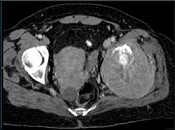

- 单项选择题男,56岁, 肺癌术后2年余,左髋部疼痛, 夜间加重,结合图像, 最可能的诊断是 ( )

B、骨转移